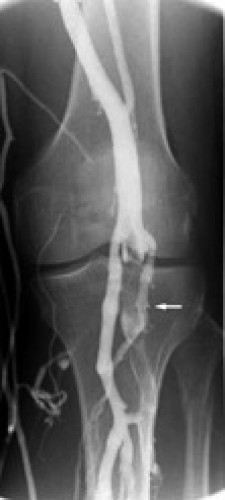

Vid förhöjd D-dimer bör ytterligare utredning göras med antingen flebografi eller ultraljud av hela benet. Kan DVT ändå inte uteslutas, tex vid proximalt ultraljud eller ofullständig flebografi, bör ett nytt proximalt ultraljud utföras efter en vecka.

Diagnostik vid misstanke om återinsjuknande i DVT: samma ben är sparsamt studerat. I Socialstyrelsens riktlinjer framkommer att diagnostik av retrombos i samma ben är vanskligt oavsett metod, och i första hand rekommenderas att man använder samma metod som vid förra insjuknandet. Ofta kan man behöva kombinera ultraljud och flebografi.

I SBU-rapporten konstateras att förekomst av posttrombotiska förändringar avsevärt försvårar möjligheten att med ultraljud påvisa eller utesluta akut djup ventrombos. Det enda säkra diagnostiska kriteriet på färsk trombos, dvs recidivtrombos, är påvisande av en konstant intraluminal fyllnadsdefekt på två flebografibilder utöver de posttrombotiska förändringarna. Jämförelse med äldre bilder är mycket värdefullt för att avgöra om trombens utbredning har ökat. I en betydande andel kan objektivt bekräftande eller uteslutande av tromb inte göras. Tidigare har man även avrått från att använda D-dimeranalys på personer med tidigare genomgången DVT, men en ny studie visar att en negativ D-dimer starkt talar mot ny DVT [5].